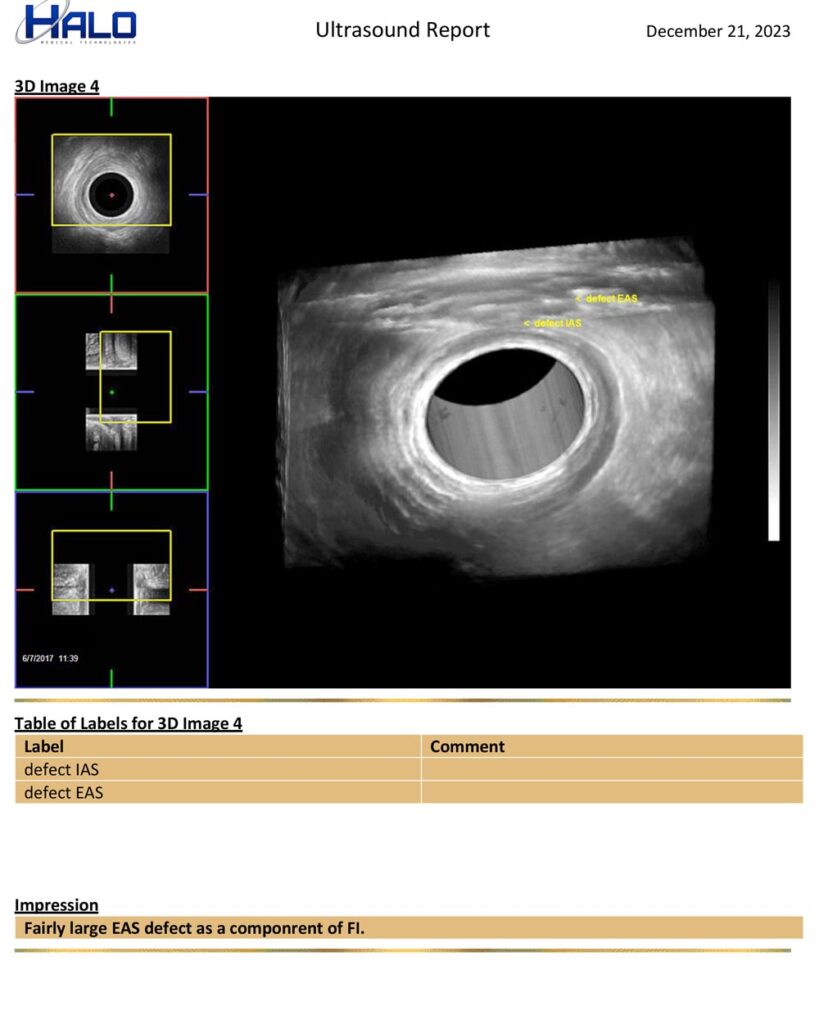

EZ-Reporter Auto-Generated Ultrasound Reports

Perform exams, mark/measure images, & document your interpretation. EZ-Reporter does the rest. The final report is auto-populated with your findings and ready for your patient’s medical record or to be sent to a referring clinician.

Sample Report